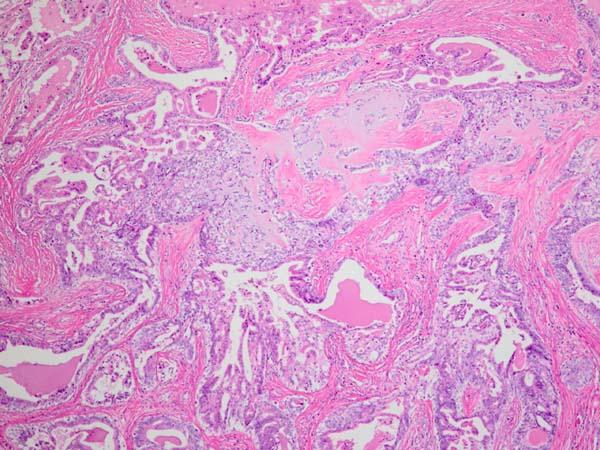

ワンちゃんが乳腺にできた複数のシコリを気にされて来院されました。bilateral mastectomyで対応しました。摘出後の病理組織検査の結果は、「右第4乳腺部:乳腺腺腫内腺癌」「左第4乳腺部:複合型乳腺癌」でそれ以外は「乳腺腺腫」でした。無事元気に退院し、その後再発もなく経過は良好です。よかったね。